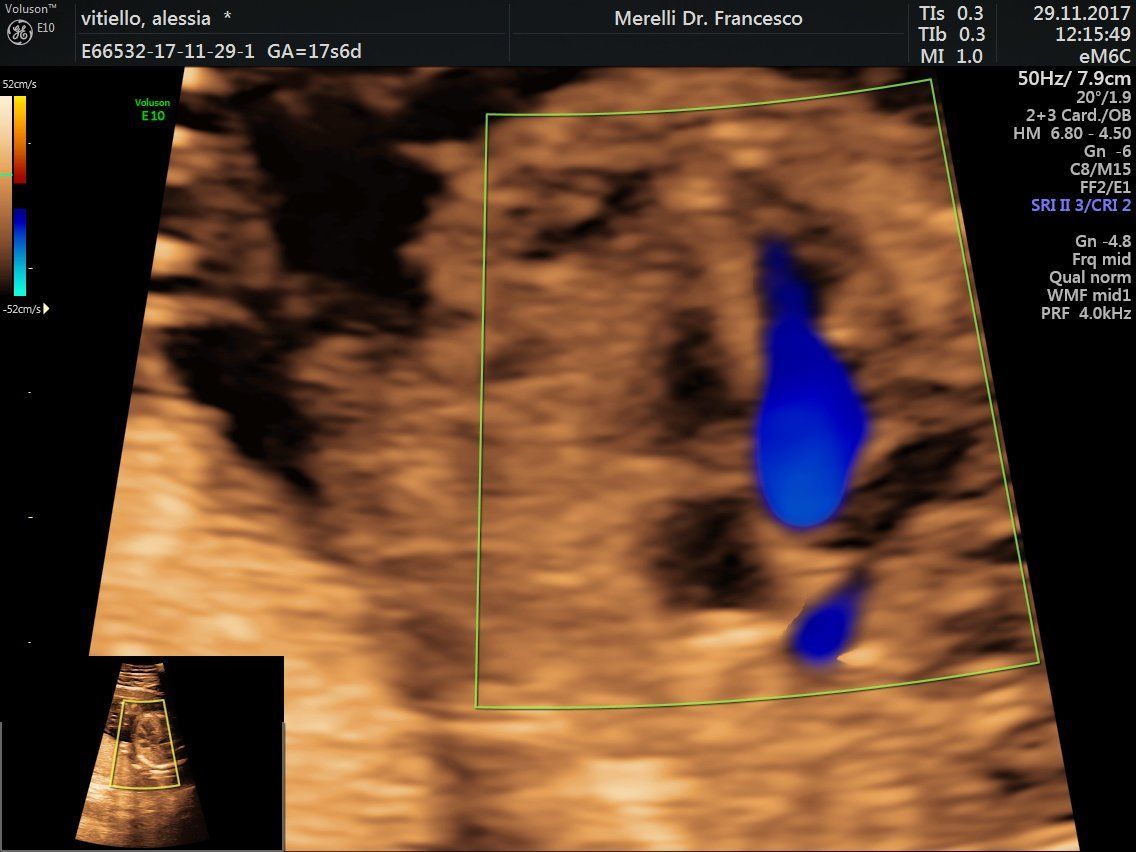

Il dr. Merelli esegue anche l'

ecografia ostetrica ginecologica tridimensionale.

- ecografie ostetrico - ginecologiche

- ecografia 4d